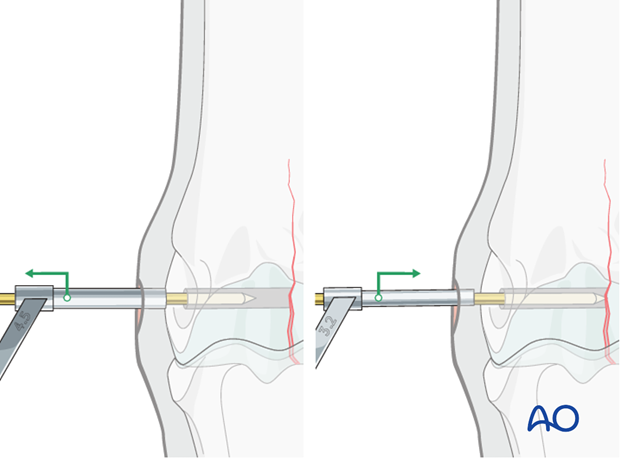

The 3.2 mm drill bit is inserted into the corresponding drill guide and the thread hole is prepared across the remainder of the bone. The drill bit should be removed and cleaned frequently because this is very dense bone.

Caution should be used when approaching the far cortex to minimize damage and debris as the drill bit exits the bone.

The 3.2 mm bit is removed and the 2.5 mm pin re-inserted. This pin is valuable to minimize any difficulties finding the hole through the stab incision.

No countersink depression is prepared because the screw head comes to lie in the epicondylar fossa. Countersinking may add additional trauma to the collateral ligament.

Note: Some surgeons nevertheless prefer to prepare a countersink depression.